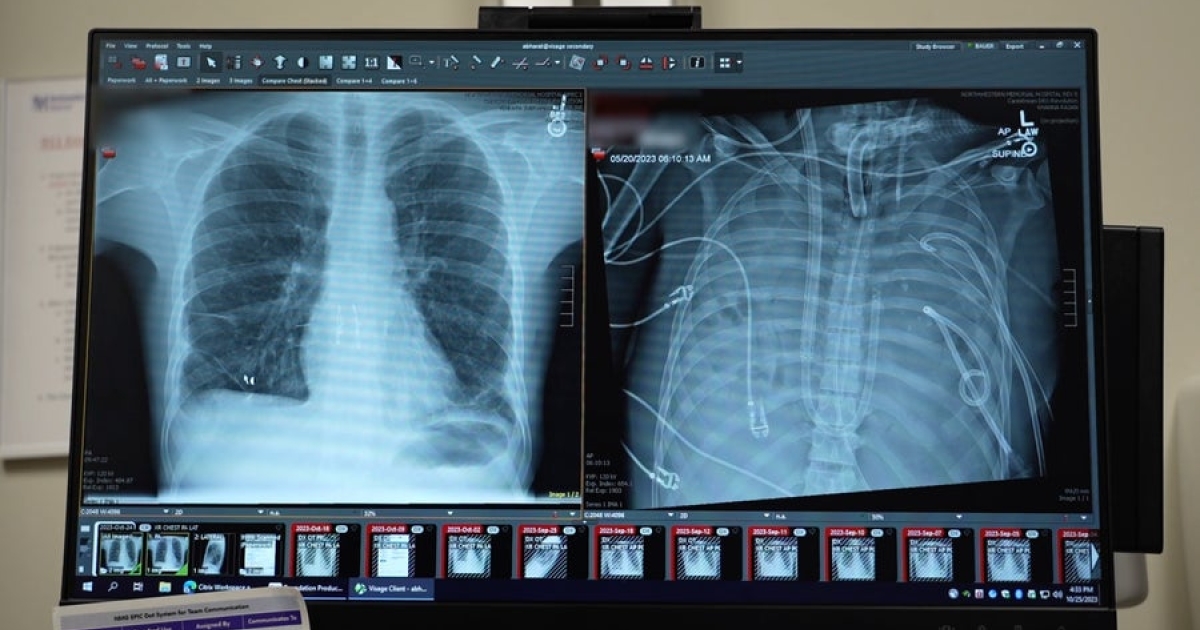

Το περιστατικό σημειώθηκε το 2023 στο Northwestern Memorial Hospital, όταν ο θωρακοχειρουργός Ankit Bharat κλήθηκε να παρακολουθεί έναν 33χρονο άνδρα με σοβαρή γρίπη, του οποίου η κατάσταση επιδεινωνόταν ραγδαία. Ο ασθενής είχε προσβληθεί από δευτερογενή λοίμωξη με Pseudomonas -ένα από τα πιο επικίνδυνα νοσοκομειακά μικρόβια- ενώ οι πνεύμονές του είχαν γεμίσει υγρό και πύον. Ταυτόχρονα, παρουσίαζε νεφρική ανεπάρκεια και η καρδιά του μόλις που λειτουργούσε.

Όταν η καρδιά του ασθενούς σταμάτησε και επανήλθε οριακά, η ιατρική ομάδα πήρε μια απόφαση χωρίς προηγούμενο. Σχεδίασαν και εφάρμοσαν ένα αυτοσχέδιο σύστημα «τεχνητών πνευμόνων», το οποίο παρέκαμπτε πλήρως το φυσικό όργανο. Το σύστημα αντλούσε αίμα από τη δεξιά πλευρά της καρδιάς, το οξυγόνωνε έξω από το σώμα και το επανέφερε στην αριστερή πλευρά, επιτρέποντας την κυκλοφορία του σε όλο το σώμα.

Ο ασθενής μπήκε στη λίστα μεταμόσχευσης και μέσα σε λίγες ώρες βρέθηκε κατάλληλος δότης. Η επέμβαση πραγματοποιήθηκε επιτυχώς και, έπειτα από εβδομάδες νοσηλείας, ο άνδρας πήρε εξιτήριο. Σήμερα, περισσότερο από δύο χρόνια αργότερα, «είναι σε εξαιρετική κατάσταση», σύμφωνα με τον γιατρό του.